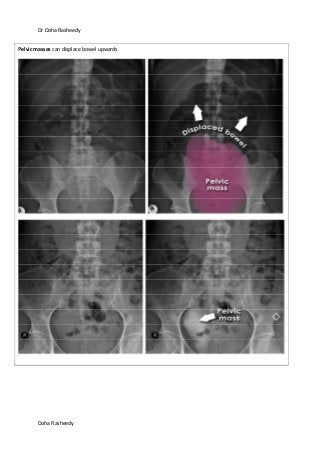

Pelvic masses can displace bowel upwards

Dr Doha Rasheedy DohaRasheedy Pelvic masses can displace bowel upwards